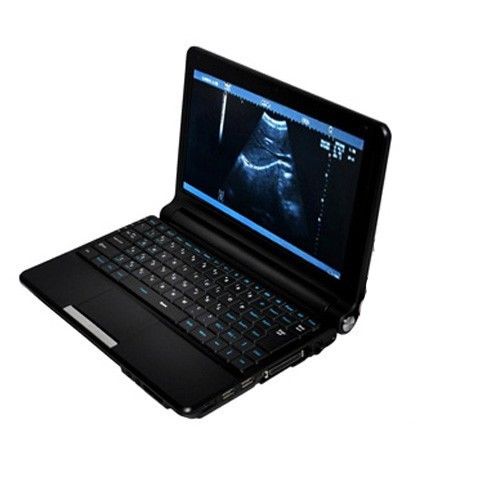

Model: RUS-9000F

Display /Monitor / Screen: 10.1-inch high-resolution TFT LCD

Video output 1: USB port 2 / MiniUSB2.0 port